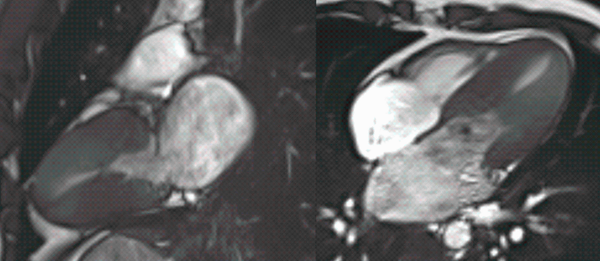

Cardiomyopathy